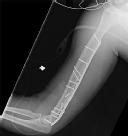

Question 19:

A 65-year-old female underwent volar locked plating for a comminuted distal radius fracture 6 months ago. The fracture has healed uneventfully. However, she now presents to the clinic with a sudden inability to actively flex the interphalangeal (IP) joint of her thumb. Which of the following technical errors during the index surgery most likely caused this complication?

Correct Answer: Placement of the volar plate distal to the watershed line

Explanation:

The patient is presenting with a spontaneous rupture of the Flexor Pollicis Longus (FPL) tendon, which is a well-documented complication of volar plating of the distal radius. It is most commonly caused by iatrogenic plate prominence due to placement of the plate distal to the 'watershed line'. This creates attrition and friction on the FPL tendon as it glides over the prominent hardware, eventually leading to rupture. Prominent dorsal screws would endanger the extensor tendons (e.g., EPL).